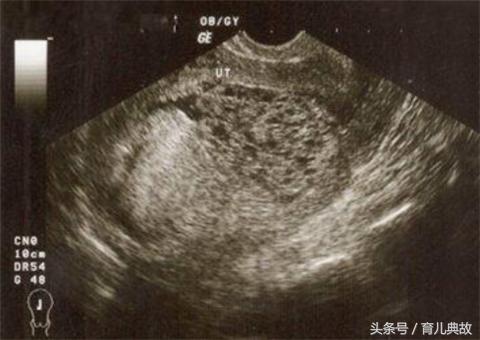

葡萄胎其实是异常受精后无法正常发育成胚胎的病变,是因妊娠后胎盘滋养细胞异常增生,间质水肿,终末绒毛转变成大小不一的水泡,相互连接成串,状如葡萄而得名。又被称为“水泡样胎块”。

5、怀的是葡萄胎时,在B超下看不到正常胎儿的形态,而是出现雪片状或蜂窝状的图片。